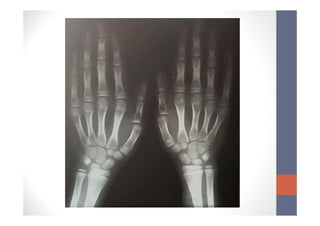

• Radiografia de mãos e punhos

• Idade óssea de cerca de 9 anos (método G. Pyle)

Caso clínico • Examecomplementares (05/11/2013) • LH: 3,12 mUI/mL (ref: <1,3) • FSH: 6,62 mUI/mL (ref: 0,11 a 1,6) • Estradiol, 17 Beta: 76,67 pg/mL (ref: 0 a 46) • USG pélvica • Útero de volume normal, visualizada esboço de linha endometrial e corpo maior que colo uterino. • Ovários de volume aumentados (OD: 4,3cm3; OE: 4,5cm3) • Radiografia de mãos e punhos • Idade óssea de cerca de 9 anos (método G. Pyle)